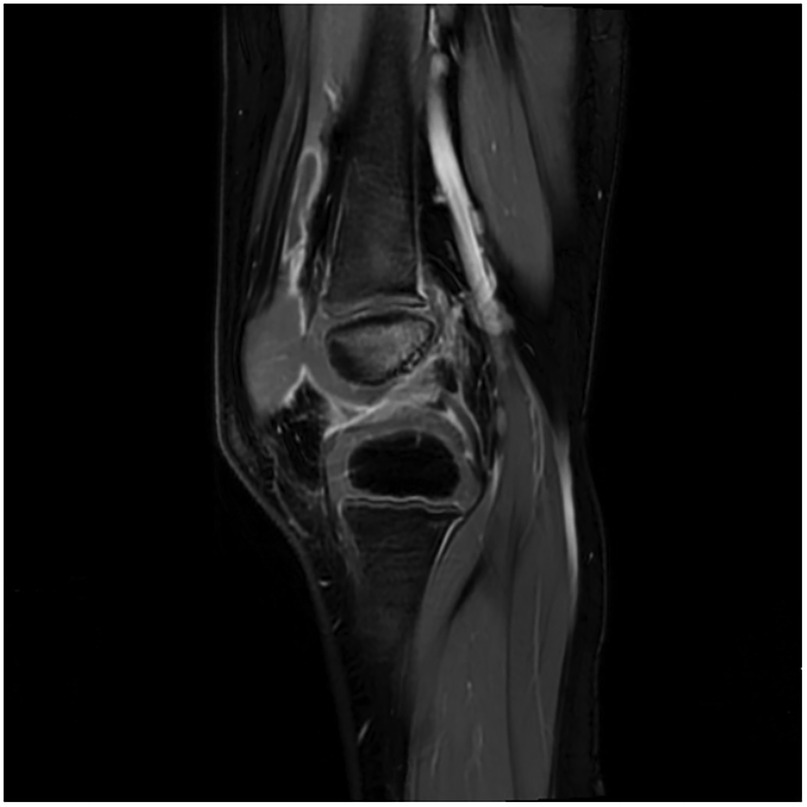

Diagnosis of Salmonella enterica-Induced Septic Arthritis in a Healthy Child Using Metagenomic Next-Generation Sequencing: A Case Report

Salmonella enterica-induced arthritis frequently manifests in children with malignancies, sickle cell disease, immunodeficiency, or undergoing immunosuppressive therapy; however, its incidence in healthy children is rare. Here, we present a case of septic arthritis resulting from S. enterica infection in a previously healthy child, diagnosed utilizing metagenomic next-generation sequencing (mNGS). This case underscores the utility of mNGS in the clinical identification of S. enterica arthritis. Particularly in scenarios where the causative pathogen remains unidentified, mNGS emerges as a pivotal adjunctive diagnostic modality for uncommon pathogens.